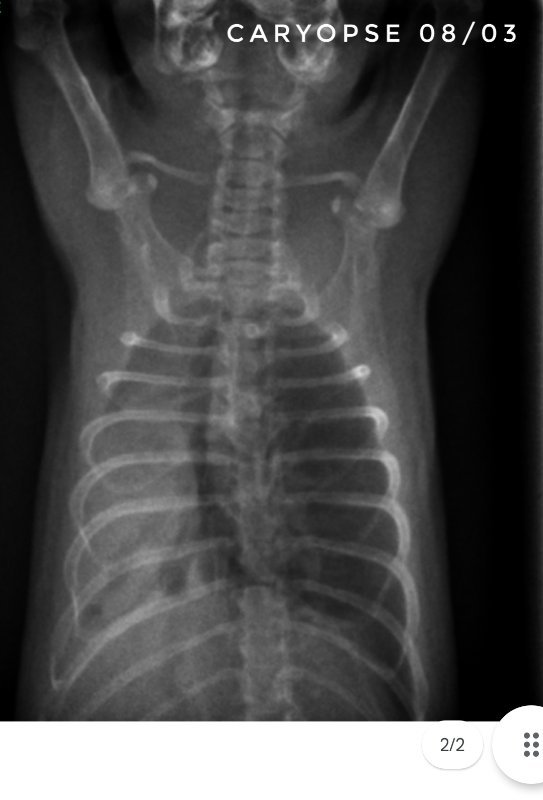

Toujours pour ceux que ça intéresse, les dernières  radios et le suivi du poids (Pyridion a commencé à perdre du poids le 04 mars, traitement changé le 08)

Bon, faudra que je vous remonte les radios de ce jour...

Il nous reste donc 3 malades : Drupe, Caryopse et Pyridion.

Drupe va vraiment mieux, poumons encore touchés mais mieux quand même (mais décidément c'est bien long).

Pyridion a eu un vrai mieux la semaine dernière et grosse dégradation là. Les radios n'ont pas bougé depuis 3 semaines...

Et Caryopse, mon petit nain (180g) va physiquement pas trop mal, c'est à dire qu'il respire vite mais pas pire quoi... par contre ses radios sont... bref, le veto ne s'y attendait pas du tout lui non plus... en gros, petit mieux là où il était touché avant mais dégradation asur le reste du poumon...